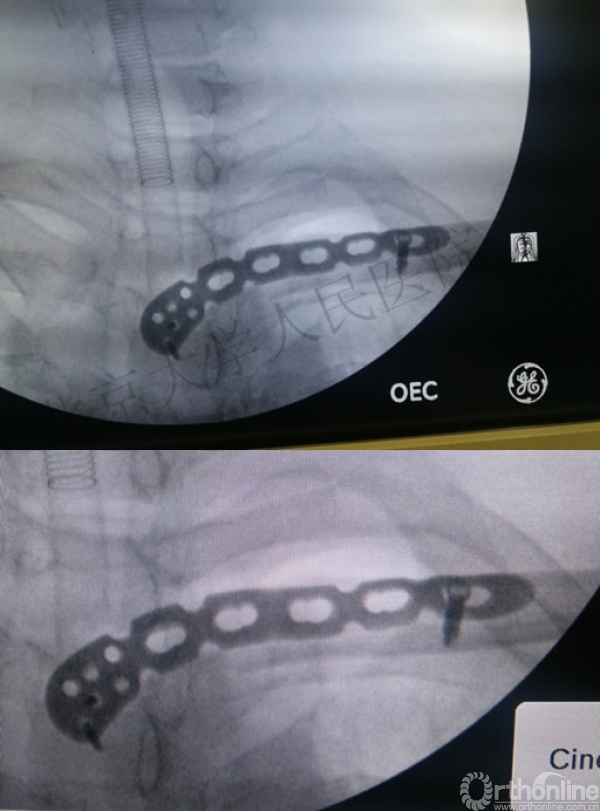

术中透视

近端骨折脱位复位难、固定难(胸骨骨质特点),借用外科缝线复位捆扎方法达到满意疗效。